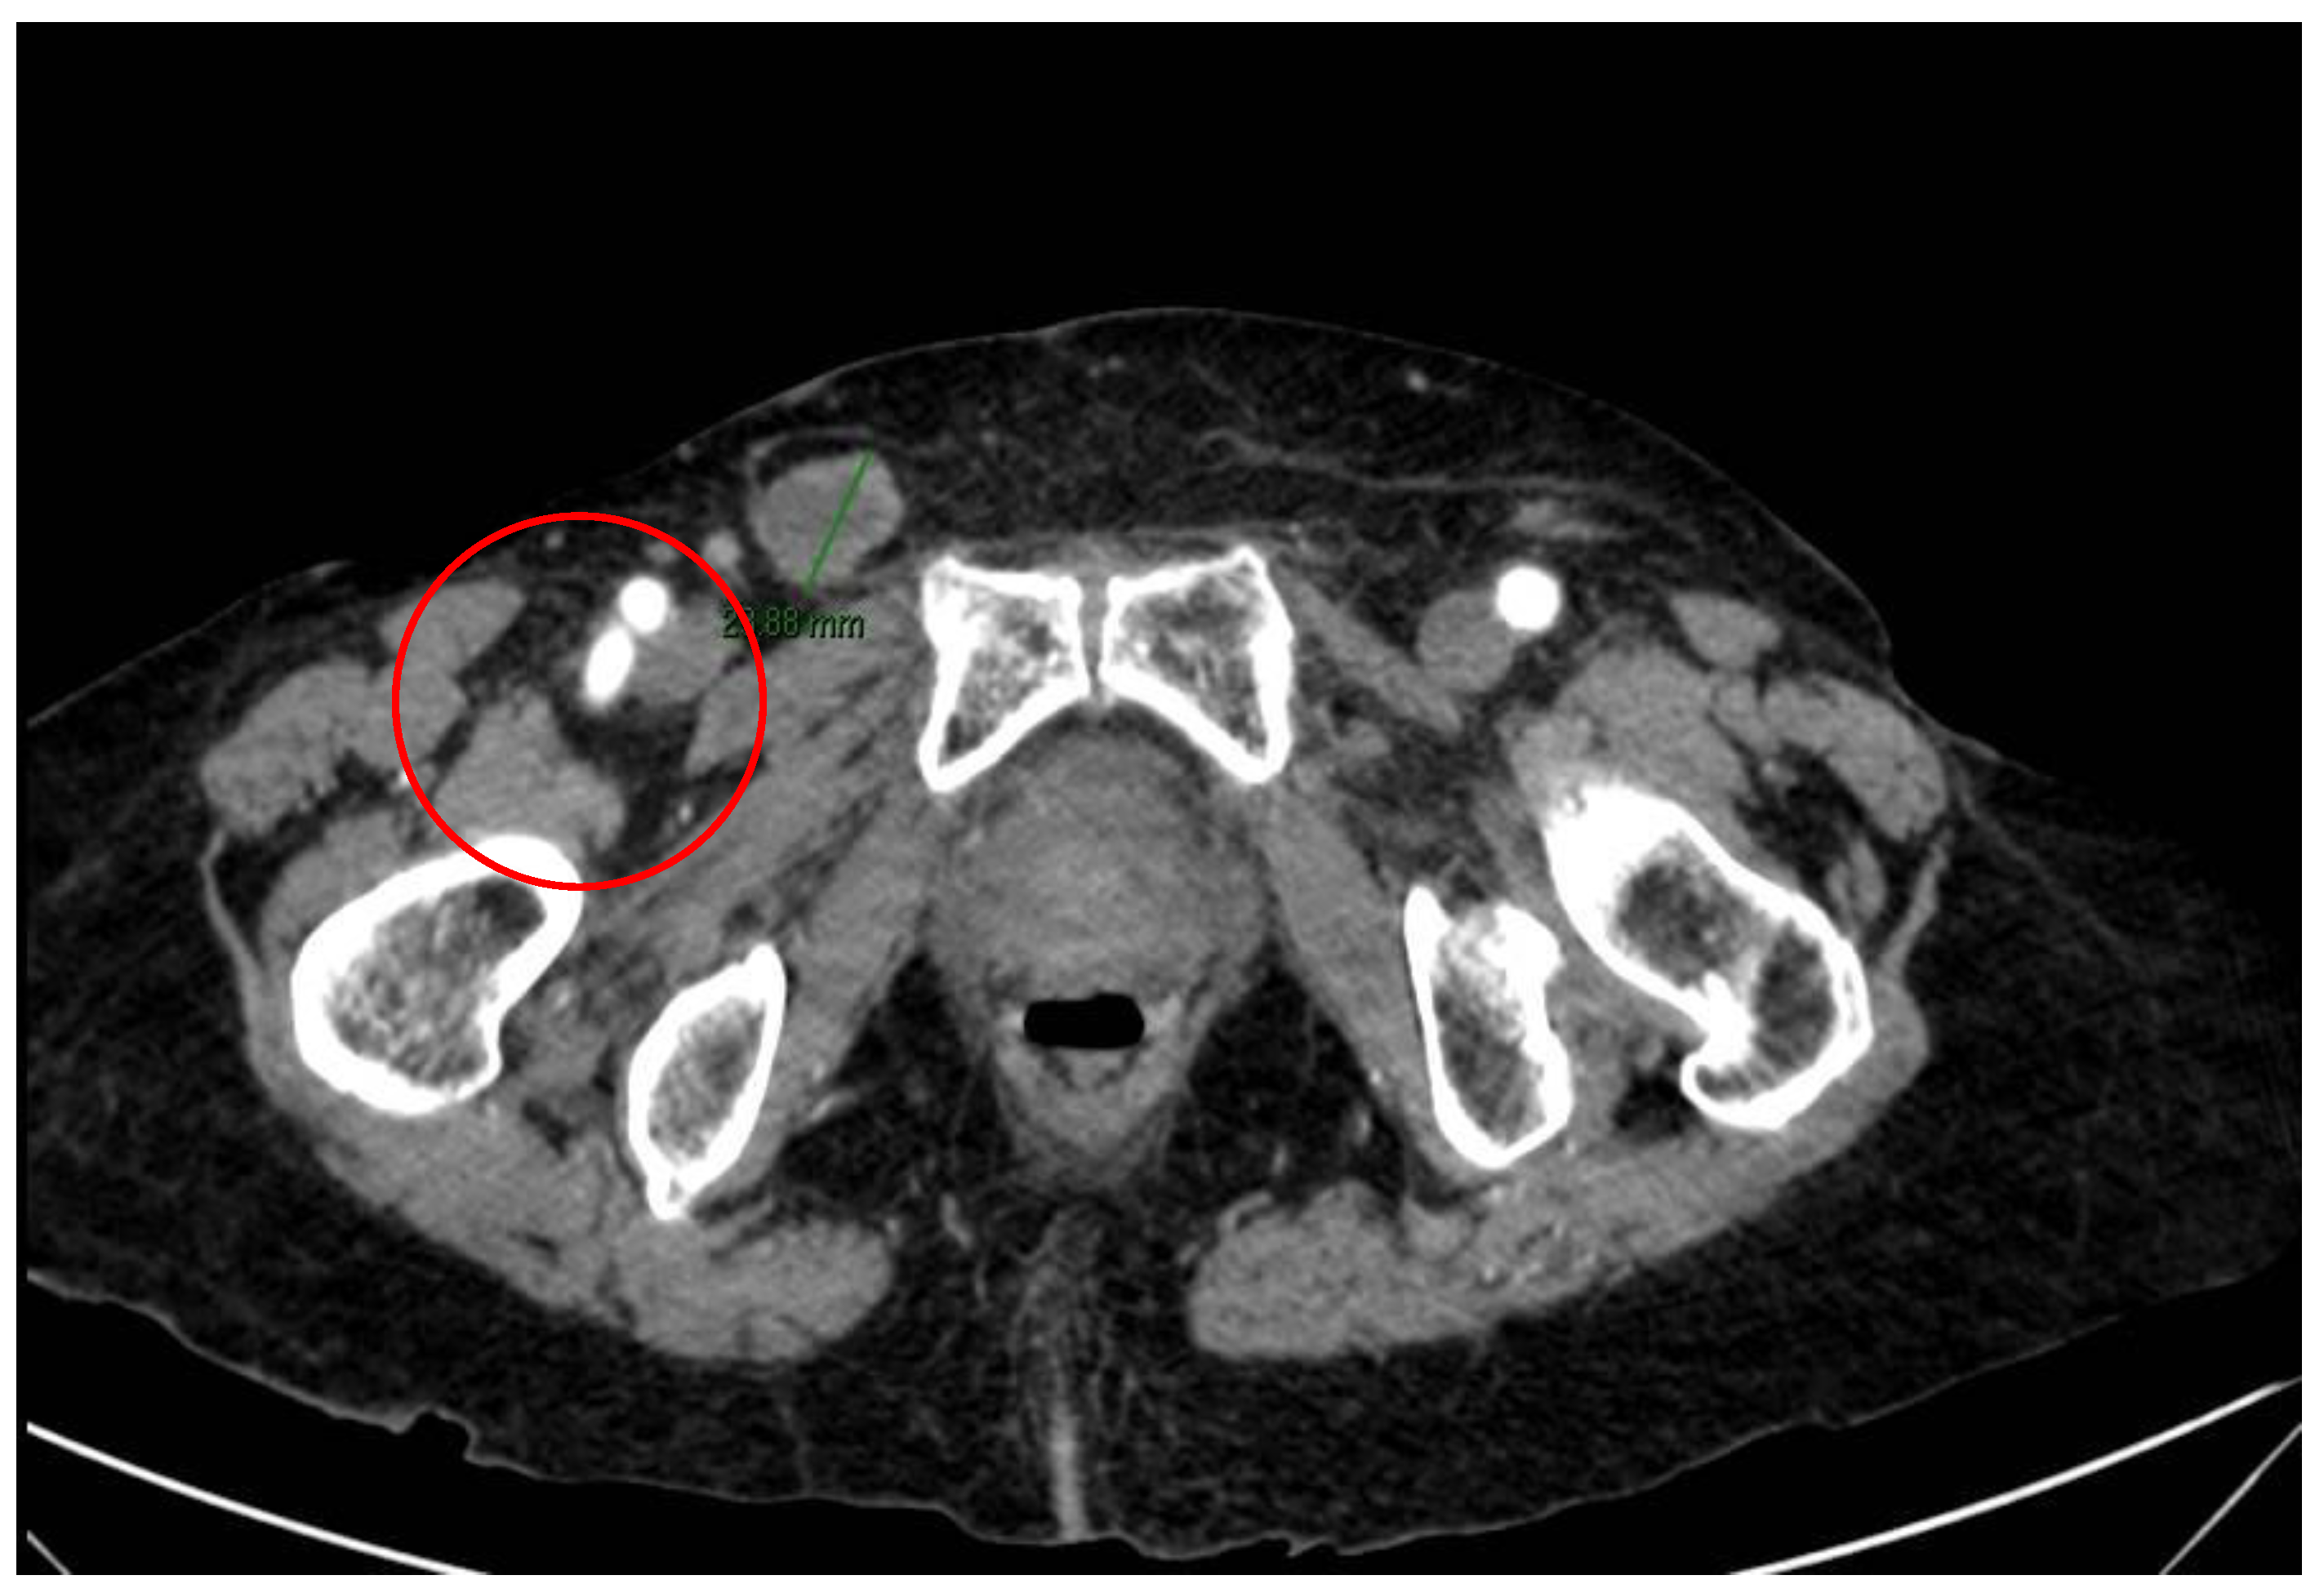

2. Case Report and Evolution